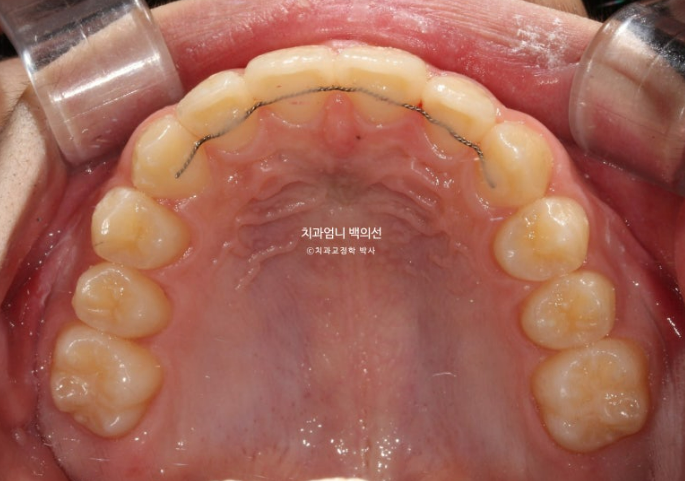

24.09

악궁모양은 예뻐졌습니다.

24.03~25.05